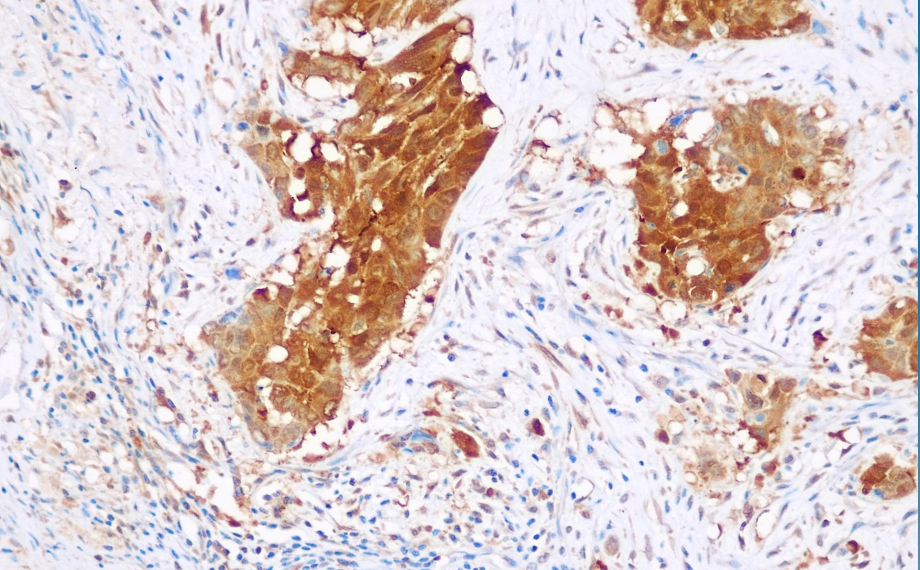

Positive control: Lung phosphor carcinoma

GST-π is a major isoenzyme within the GST family, distributed throughout various organs in the body, with higher concentrations in the liver and kidneys, and is associated with liver detoxification functions. It primarily catalyzes the reaction between GSH and electrophilic substances to form GS-X, which is then excreted outside the cell to achieve detoxification effects. GST-π is highly expressed in various tumors, and it is currently believed to be associated with tumor resistance to drugs such as doxorubicin, cisplatin, nitrogen mustard, cyclophosphamide, and tamoxifen. This antibody is primarily used for research into tumor cell resistance.

GSTπ antibody reagents can specifically bind to GSTπ molecular antigens. Immunohistochemistry kits containing GSTπ antibody reagents are suitable for assessing and predicting tumor chemotherapy resistance and platinum or multidrug resistance.